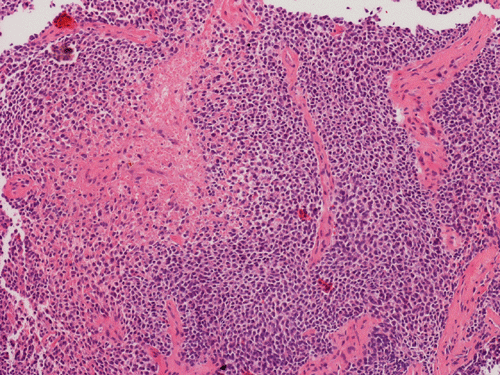

A. Hematoxylin & Eosin

B. Hematoxylin & Eosin

C. Hematoxylin & Eosin

Pathology of the Case: Essentially, this is a small blue cell tumor with focal necrosis (Panel A and B). The nuclei are rather monotonous. Please note that the nuclei are slightly larger than most so-called small blue cell tumor such as small cell carcinoma of the lung. The tumor arrange in solid sheets without any pattern formation. There is a gap in between the cells. This is not uncommon in Ewing sarcoma. However, this pattern can also be seen in hematopoietic tumors such as lymphoma and plasmacytoma. In some areas, some of the tumor cells have a small rim of cytoplasm and some of these rims appear to be formed by fused minute bubbles (Arrow in Panel C). Results of speical stains, immunohistochemistry and molecular studies are as follow:

Ewing sarcoma belongs to the family of non-hematologic small round cell tumor characterize by small, undifferentiated, cells with hyperchromatic nuclei. Rosettes similar to Homer Wright rosettes are occasionally present but tumor cells usually arrange in solid sheets. Densely packed solid sheets of small round cells with minimal to no interlacing collagenous collagen or stromal component is the classic appearance. These tumors are richly vascularized by a delicate network but it is not obvious because of compression of vessels by tumor cells. Typically, no inflammatory cells are present. Necrosis is a typically present.

Tumor cells are fairly uniform and have a small amount of cytoplasm typically in the form of a thin rim. Intercellular gaps that are often seen in hematopoietic neoplasms may be present. Cytoplasmic vacuoles corresponding to the glycogen vacuoles can be well appreciated in cytologic preparations. However, it is hard to differentiate them from fixation artifacts in permanent sections. Ewing sarcoma typically contains a good amount of glycogen that are well demonstrated by PAS stain with and without diastase pre-digestion. The nuclear chromatin is finely granular. Although it is a small round cell tumor, its nuclei tend to be marginally larger and less crumbled than many of the other small round cell tumors such as small cell carcinoma. It is common to have geographic patches of cells with open chromatin alternating with areas with closed chromatin leading to a biphasic dark cells and light cells pattern. Small but identifiable small to moderately sized nucleoli. Large and prominent nucleoli can be seen in large cell Ewing sarcoma. Otherwise, large and prominent nucleoli are not typical for Ewing sarcoma.